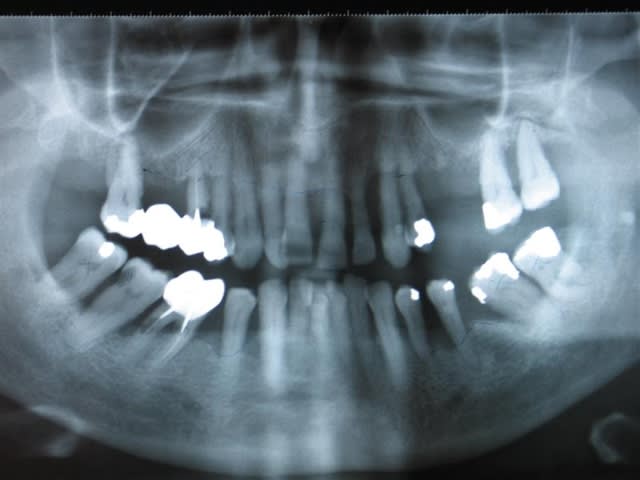

Patiente de 62 ans, adressé par un confrère qui ne peut plus faire grand chose pour elle, et me l'envoi pour implant.

C'est une situation que je trouve bordeline.

En bas, je pense ext les molaires, faire paro, odf light et implants.

En haut, j'hésite : donc, soit :

1 : paro style charon, bridge 17-16-15-14, ext sans doute 27 28, implant + sinus 25 26 27, odf pour corriger les migrations paro.

( malgré la perte osseuse et les poches profonde, il y a peu de mobilité, a part les molaires. évidement, moult spiro, amibe et autres bestioles )

Plus sérieusement, je n'ai ni rétroalvéolaires, ni mesures de la mobilité de ces dents, mais avec certaines alvéolyses atteignant les 2/3 des dents, c'est tout de même mal barré.